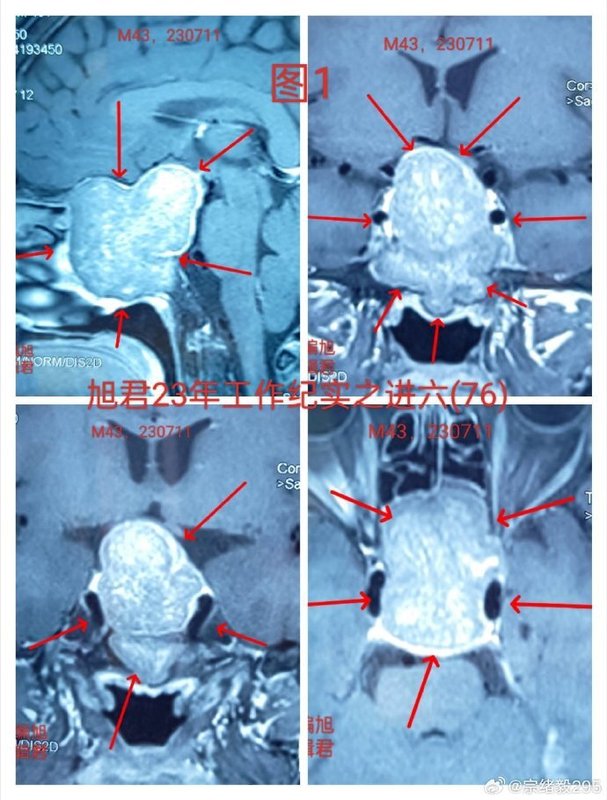

某位43歲的患者因頭痛和視物不清的癥狀而接受了CT和MR檢查,結果顯示患有一種巨大的侵襲性垂體腺瘤,該腺瘤向顱內擴散,主要侵襲了蝶竇并充滿了蝶竇空間,見下【圖1-2】。手術采取內鏡經鼻蝶微創(chuàng)切除腫瘤。手術中最大的難度在于腫瘤的侵襲性質,特別是其填滿了蝶竇。在成功切除腫瘤后,面臨的主要問題是處理較大的瘤腔創(chuàng)面和止血,其次是應對鞍底骨質和硬膜的破壞,還需要同時確保鞍隔的完整性得到保護。不過這些關鍵步驟都處理得非常好。手術后,腫瘤被滿意地切除,見下【圖-3】,患者恢復情況良好。